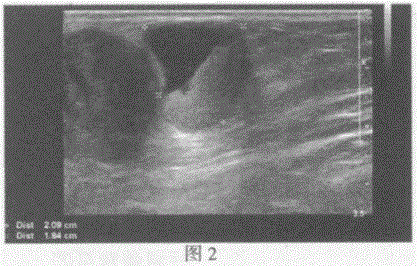

问题 临床资料:女,70岁,自诉确诊左足底恶性黑色素瘤两年余,中药治疗无明显好转来诊。 超声综合描述:左腹股沟区可见多个低回声(图1),部分相互融合,最大3.5cm×2.1cm,边界清晰,形态不规则,内回声不均,CDFI:内可见血流信号。左腹股沟区另可见多个不均质回声区(图2),最大2.1cm×1.8cm,边界清晰,形态不规则,内可见无回声区,CDFI:不均质回声区内可见血流信号。 超声提示: